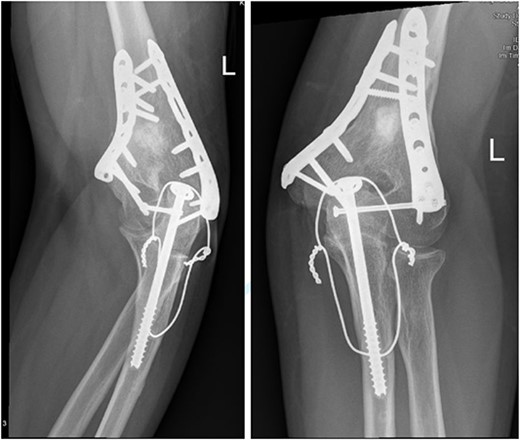

Upon arrival the patient underwent exploratory laparotomy followed by irrigation and debridement of both femur and humerus and application of external fixators (Fig. 2). The patient was admitted to the intensive care unit (ICU). Two days later, the patient underwent open reduction and internal fixation of both proximal and distal humerus (Fig. 3).

Anteroposterior (AP) view of the left humerus and elbow after Ex-fix application.